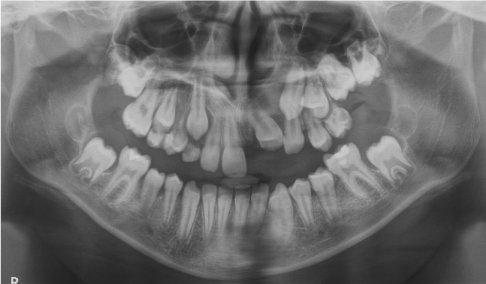

Marsupialization of the cystic lesion with avulsion of the deciduous elements involved in the lesion area is proposed, following which a lingual arch is applied to maintain the space for erupting teeth. After three and six months Ortopantomography was performed in order to check the evolution of the healing process and the eruption of the impacted tooth (Figures 7,8). Nine months from surgery 4.2 erupted and no cyst lesion was observed (Figure 9).

Figure 7 Case 2. Three months after marsupialization

Figure 8 Case 2. Six months after marsupialization.

Figure 9 Case 2. After nine months  there is no cystic lesion and the element displaced are erupted

Figure 6 Case 2. Initial ortopantomography